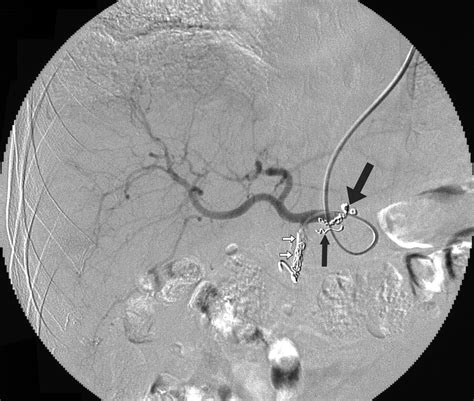

Imaging techniques play a vital role in evaluating the health and patency of the Left Gastric Artery. Computed Tomography (CT) scans with contrast enhancement are the gold standard for visualizing the vessel’s diameter and identifying any aneurysms or atherosclerotic changes. In cases of acute hemorrhage, angiography allows for both the diagnosis and immediate therapeutic intervention via transcatheter arterial embolization.

Physicians must maintain a high index of suspicion for vascular involvement in patients presenting with hematemesis or melena. Early identification of the vessel status through diagnostic imaging can guide the treatment team toward the most effective management strategy, whether it be endoscopic clipping, surgical ligation, or endovascular embolization.